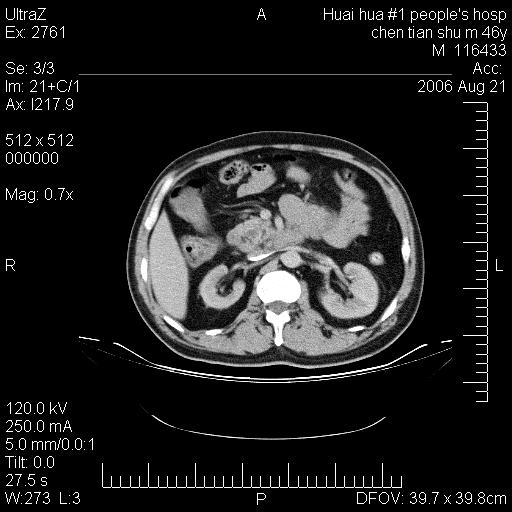

患者,男,46y。腹痛2月,消瘦。

十二指肠水平段占位,考虑间质瘤或平滑肌瘤。

肿块较大,腹膜后占位,境界欠清,周边脂肪密度较高呈条状影,有没有脂肪肉瘤可能,

缺少完整的三期图像。考虑肠系膜脂膜炎mp(肿块型)。

鉴别:间质瘤(这么大而无囊变不可思议)、平滑肌瘤/肉瘤、淋巴瘤、类癌,脂肪类肿瘤、转移瘤等。

十二指肠水平段占位,考虑间质瘤。

首先考虑小肠间质瘤。

十二指肠水平段软组织密度占位,考虑间质瘤可能性大。

腹膜后占位,境界欠清,考虑来源于十二指肠病变,间质瘤或平滑肌肉瘤可能性大。建议活检。

手术病理结果:原发性小肠恶性淋巴瘤(primary gastrointestinal lymphoma,pgil)是原发于胃肠的淋巴网织系统的恶性肿瘤,在结外淋巴瘤中居第一位,该病少见,临床无特异性,诊断困难,术前主要依靠影像学诊断。胃肠道本身具有较丰富的淋巴组织,因而胃肠原发性淋巴瘤是结外淋巴瘤最常见的部位,文献报道约占胃肠道恶性肿瘤的1%~4%,其中胃约占50%~70%,小肠约占35%~70%,结肠约占4%~6%。影像检查在pgil的诊断及分期中有重要的作用,ct是很有价值的检查方法。

胃肠淋巴瘤病理特点:胃肠道原发性淋巴瘤起源于胃肠壁固有层和黏膜下层的淋巴组织即胃肠粘膜相关淋巴组织(malt),多为粘膜相关淋巴瘤。病理上通常为非霍奇金淋巴瘤,且决大多数来源于b淋巴细胞,很少见于霍奇金淋巴瘤。胃肠原发淋巴瘤比胃肠道癌的发病率要低的多,最常见于胃,其病因可能跟幽门螺杆菌感染有关。幽门螺杆菌能引起胃粘膜损害,引起炎性及免疫反应,淋巴细胞聚集并形成滤泡,可影响胃的正常生理功能,导致胃淋巴瘤的发生。单纯性小肠淋巴瘤是常见好发于回盲末端,受累的肠段较长,可单发、多发,甚至累及整个小肠。原发性大肠淋巴瘤罕见,以直肠和盲肠最多见。病变大体观可表现为胃肠腔内外的肿块,也可表现为从黏膜下到浆膜面肠壁的纵向浸润,并且常常伴有肠系膜淋巴结肿大。任何情况下,肿瘤几乎总是导致一定程度的肠壁增厚,可对称或不对称,病变与正常组织间常无明确分界,肠腔可狭窄、正常或动脉瘤样扩张,后者主要是肿瘤在肠壁内浸润,破坏肠壁内植物神经丛所致。以上改变成为ct检测病变的病理基础。

肠道淋巴瘤的ct表现分为4类

1) 壁内浸润型, (2)多发结节型, (3)肠系膜受累伴腔外肿块型(本型就是),(4)肿块型。